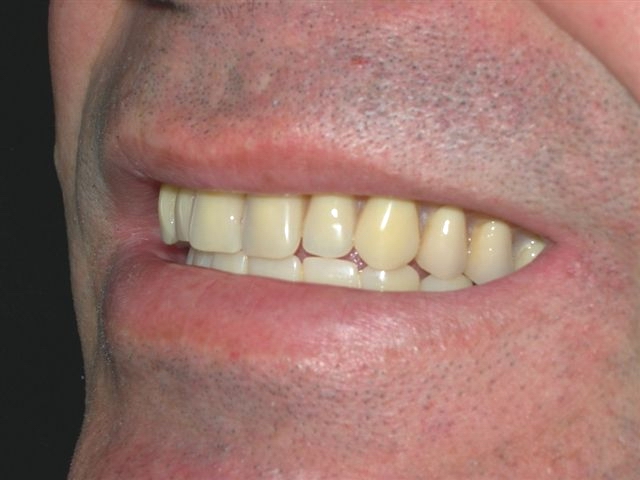

Prova de articulação em boca (montagem em cera sobre barra metálica) (vista lateral direita)